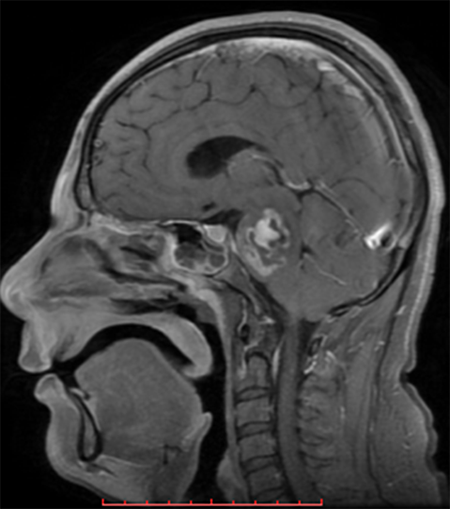

h. 2) Resonancia magnética cerebral de corte axial en secuencia T1 con gadolinio. Se identificó a nivel del puente y pedúnculos cerebolosos una imagen con efecto de masa y reforzamiento en el interior; en el hemisferio izquierdo se observó una imagen heterogénea, con zonas de reforzamiento al medio de contraste en el interior. (Figura 2).

Figura 2. Resonancia magnética cerebral corte axial en secuencia T1 con gadolinio.